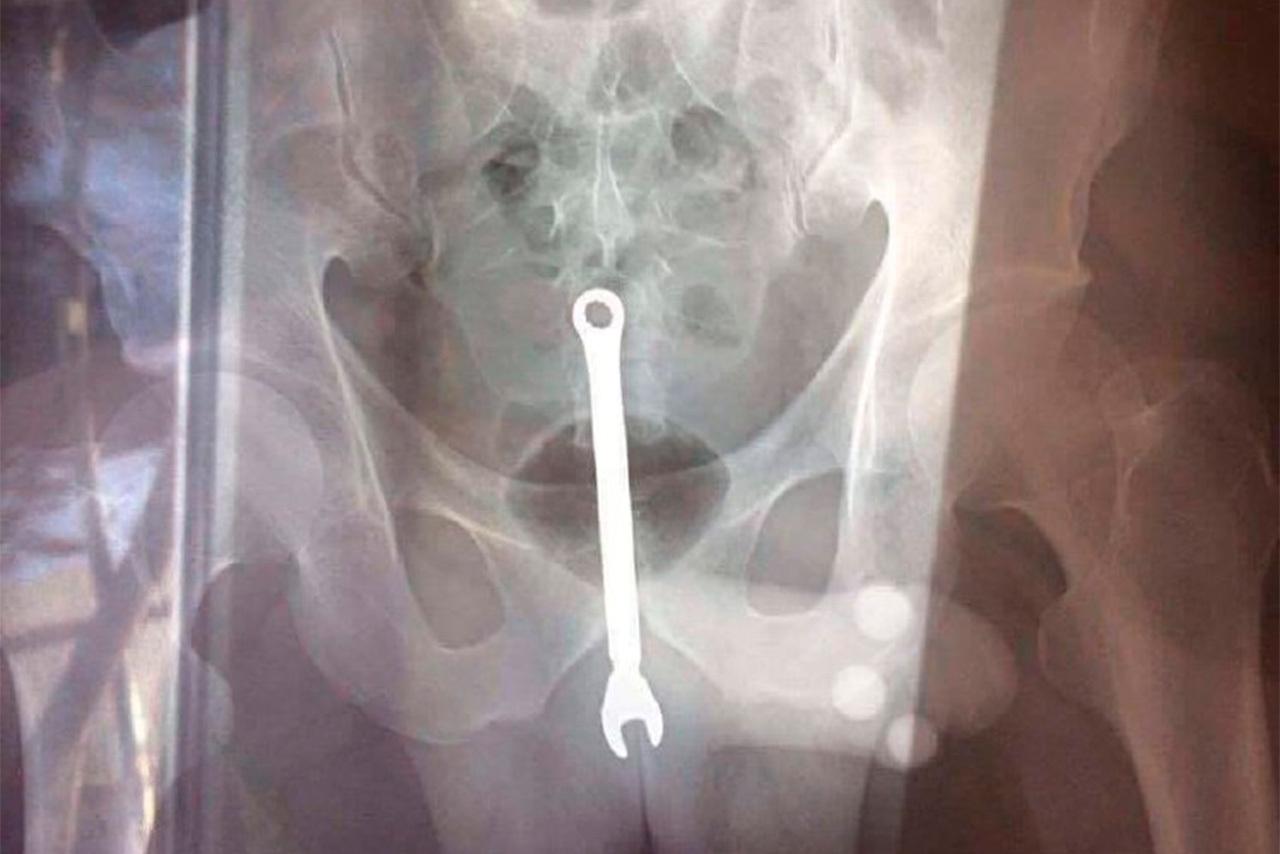

Что только не застревает в заднем проходе человека из-за садистских удовольствий либо случайно . Ниже представляем 10 самых нелепых предметов, которые застревали в заднем проходе человека . 1 . БУТЫЛКА Фермеры могут . . .